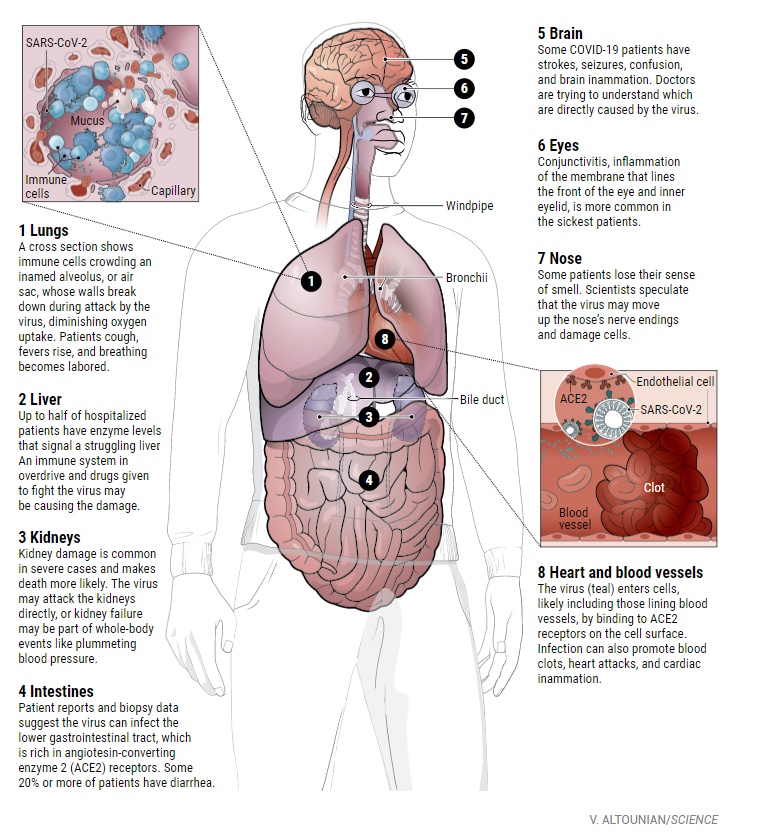

他们意识到,虽然肺部是受感染最严重的器官,但它可以延伸到包括心脏和血管、肾脏、肠道和大脑在内的许多其他器官。

耶鲁大学和耶鲁-纽黑文医院的心脏病学家Harlan Krumholz说:“这种疾病几乎可以攻击人体内的任何一样组织器官,这种持续性攻击的结果将是毁灭性的。”

虽然SARS-CoV-2会进入肺部,对肺部造成严重损害,但是实际上病毒影响范围不仅局限于肺部。科学家们才刚刚开始探索这种危害的范围和性质。

与此同时,一些科学家正在把注意力集中在一个完全不同的器官系统上——心脏和血管(心血管系统)。他们认为,这个系统才是导致一些病人病情迅速恶化的原因。

病毒到底是如何攻击心脏和血管的,至今仍是一个谜。但数十份的研究和论文证明这种损害在COVID-19患者中是很常见的。

3月25日发表在《JAMA Cardiology》(《美国医学会杂志心脏病学》)上的一篇论文记录了中国武汉416例住院的COVID-19患者中近20%的患者出现了心脏损伤,而另一篇在武汉的研究表明,36名ICU病人中有44%患者伴有心律失常。

这种破坏似乎延伸到了血液。根据4月10日发表在《Thrombosis Research》杂志上的一篇论文显示,在一家荷兰重症监护病房的184名COVID-19患者中,38%的患者血液凝结异常,近三分之一的患者已经有了血栓。

血凝块会破裂并落在肺部,阻塞重要的动脉,这种情况被称为肺栓塞,据报道已经有19名患者死于这种情况。

动脉血栓也会进入大脑,导致中风。哥伦比亚大学医学中心(Columbia University Medical Center)心血管医学研究员Behnood Bikdeli发现,许多病人体内D -二聚体(D -dimer)含量非常高,而D -二聚体是血凝块的副产品。

纽约大学朗格尼医学中心的神经学家Jennifer Frontera说:“一般而言,COVID-19患者不是死于肺衰竭,他们就是死于肾衰竭。”肾脏由于富含ACE2受体,因此可能成为另一个病毒的靶器官。

COVID-19患者的另一组显著的症状集中在大脑和中枢神经系统。Frontera说,在所在的医院中有5%到10%的COVID-19患者需要神经科医生协助治疗。

Fronter见过COVID-19患者伴有脑炎、癫痫和“交感神经风暴”(交感神经系统的过度反应会导致癫痫样症状,通常见于脑外伤后的患者),还有一些COVID-19的患者会短暂地失去意识、中风、失去嗅觉等症状。

约翰斯·霍普金斯医学院(Johns Hopkins Medicine)的重症监护医师Robert Stevens说,ACE2受体同样存在于神经皮层和脑干中,但尚不清楚病毒是在什么情况下进入大脑并与这些受体相互作用的。

但其他因素可能会损害大脑。例如,细胞因子风暴可能导致脑肿胀,血液凝块的剥离可能引发中风。

实际上越来越多的证据表明,这种新型冠状病毒,可以感染下消化道的内壁,因为消化道细胞同样含有大量的ACE2受体。目前在多达53%的患者粪便样本中发现了病毒RNA。

肠道并不是疾病在体内传播的终点。目前,超过三分之一的住院病人患上了结膜炎;其他报告显示患者伴有肝损伤;在中国两个中心住院的COVID-19患者中,超过一半的人体内的酶水平升高,表明肝或胆管损伤。